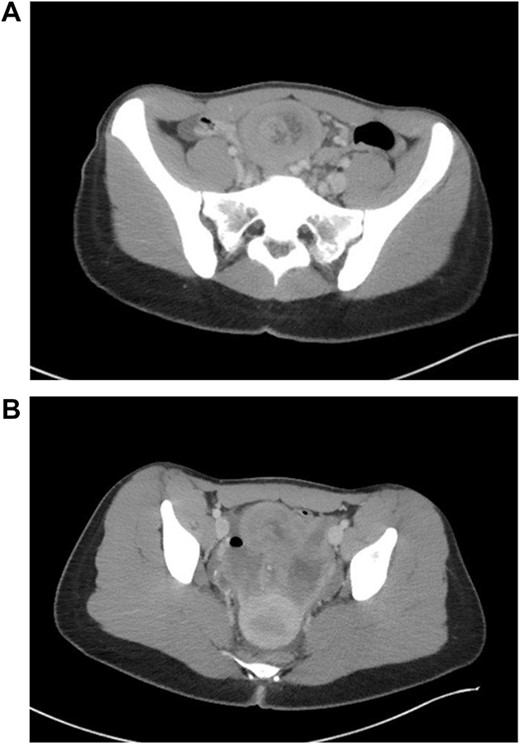

The patient was tolerating a diet, and experiencing anterograde bowel function on postop Day 9; however, the decision was made to obtain a CT of the abdomen pelvis due to an increasing leukocytosis shift. CT revealed two fluid collections with gas pockets, anteriorly measuring 4.0 × 2.8 cm, 9.8 × 6.3 cm in the rectal space (Fig. 3).